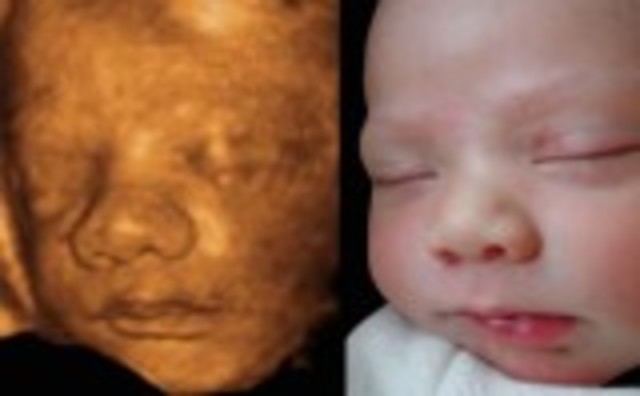

• Week 27: Eyes Can Open

Week 27: Eyes Can Open

Fetus weighs almost 2 pounds and is about 14.5 inches long, head is over 2.5 inches in diameter, baby's hearing continues to develop, eyes can blink open and close